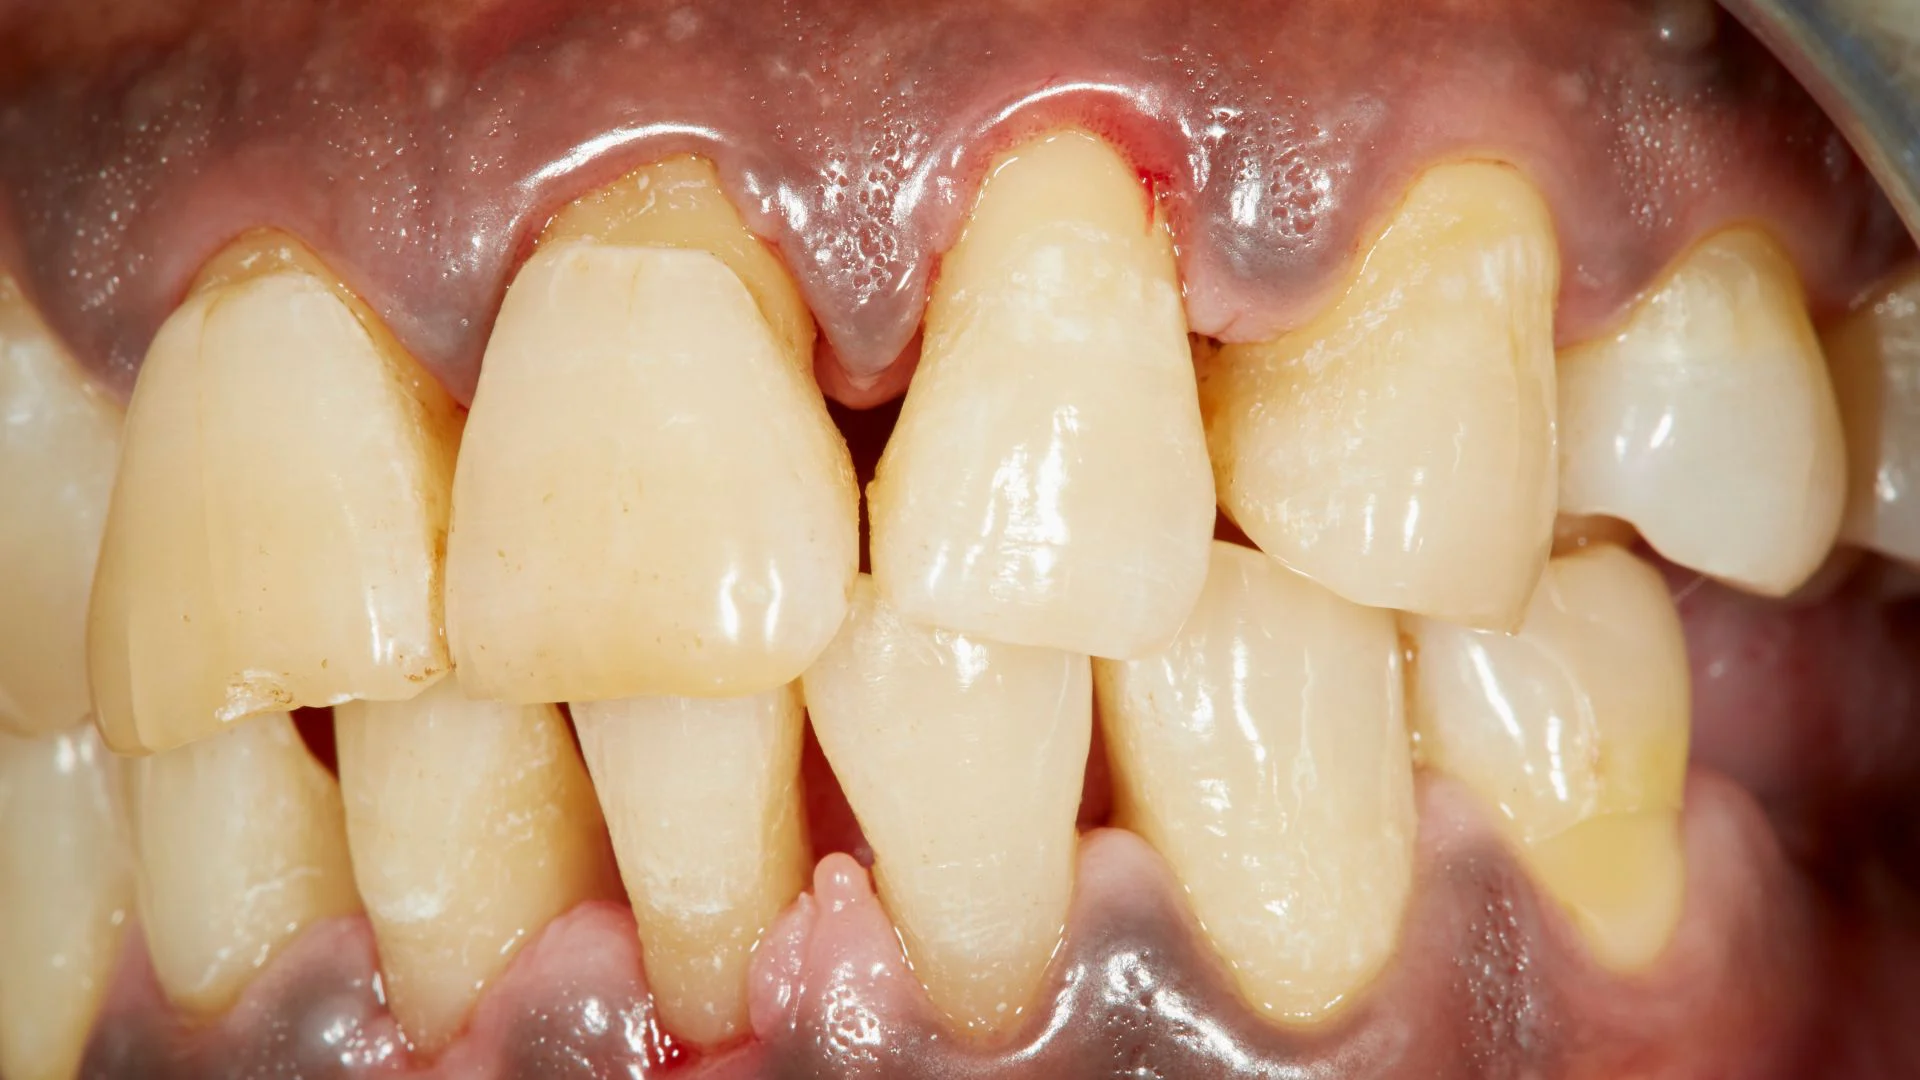

Wij verlenen tandheelkundige zorg in brede zin.